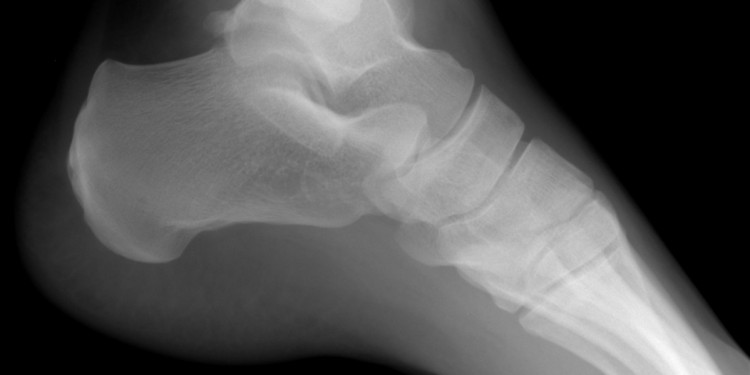

Talus Kırığı

Talus kalkaneustan sonra ayağın ikinci büyük kemiği ve en sık yaralanan ikinci kemiğidir. Talus ayakta kas yapışmayan tek kemiktir, malleol ve ligamentlerle yerinde tutulur.Talus kırıkları genellikle aşırı dorsifleksion ya da önemli yükseklikten düşme gibi önemli mekanizmalar gerektirir. Küçük kırıklar ayaktan, posterior atel, üzerine basmama, analjezi ve ortopediye yönlendirme ile tedavi edilebilir.

Talus boyun ve başını içeren büyük kırıklar acil ortopedi konsültasyonu gerektirir. Bu tarz yaralanmalarda avasküler nekroz yüksek oranı yüksektir. Kırıklar plantar fleksiyon, dorsifleksiyon veya inversiyon güçleri sonucu olabilir. Talus kırıkları genellikle yüksek enerjili travmalarla oluşur ve beraberinde ayak, diz ve vertebra yaralanmarı sıktır.

Grafi: Kubbe kırığı durumunda belirgin bir kırık hattı görülebilir, fakat yaygın olarak bir osteokondral yaralanmanın düz radyografide görülmesi zordur. Os trigonum (talus posterior yüzündeki aksesuar kemik) kırıklarının da düz radyografiler ile görüntülenmesi zordur.

Düz grafiler belirsiz kırıkları kaçırabilir ve BT ve MRI gerekebilir.